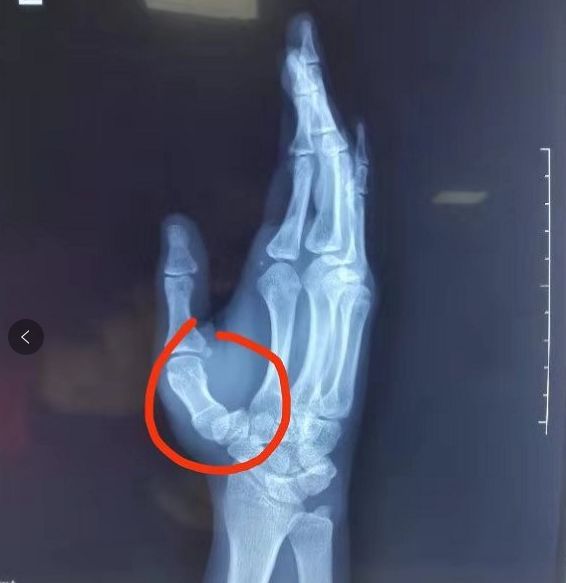

一位运动员在国外滑雪训练时,手指杵在雪地里。我赶过去查看,发现这位运动员左手第1掌指关节肿胀,虎口区较右侧增宽,触摸第1掌骨连续性良好,无骨折体征。凭借我的判断是肯定有问题,但是又不能确定是什么问题。遂带其前往当地医院就诊,经X片检查,值班医生诊断为第1掌骨远端骨折,建议打个石膏。作为一名年轻骨科医生我不同意其诊断,总觉腕掌关节有问题,但是又拿不准。我坚持在德尔康尼所学,医学问题不能含糊,不能盲目治疗。

我突然想起出发前院领导郑重强调的“无论何时,无论你身在何处,无论有什么困难医院都会是你强大的后盾”。我随即将患者的片子及病例通过微信汇报给医院,德尔康尼的各位主任很快给予我指点以及专业的治疗建议,让我感觉豁然开朗。经过研究,我们确定这位运动员是“第一掌腕关节脱位”,随后我按照上级医师教我的方法,徒手予以复位(第一次复位这种关节脱位),随着“咔嗒”的响声和强烈的复位感,这位运动员之前的胀痛感减轻大半,虎口畸形消失,手腕、手指活动恢复。然后我自制固定装置予以妥善固定。治疗完成,我内心充满了成就感,因为我知道,我的努力帮助一位国家队的运动员恢复了健康。